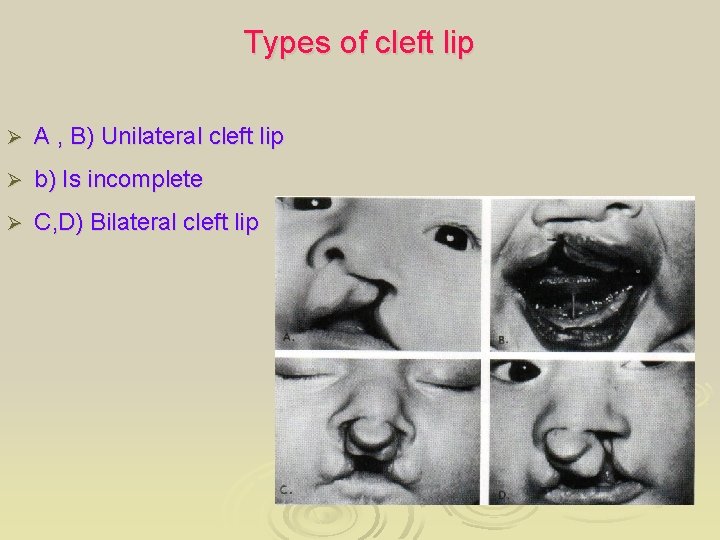

Types of cleft lip Ø A , B) Unilateral cleft lip Ø b) Is incomplete Ø C, D) Bilateral cleft lip